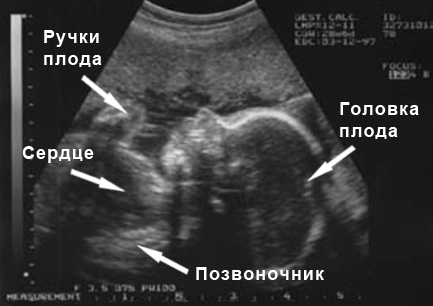

УЗИ на 28 неделе беременности

У женщин с нормальным течением беременности плановое УЗИ на 28-й неделе обычно не проводится. Однако в некоторых случаях его могут назначить для определения положения ребенка в матке. Плод продолжает активно расти, и пространство в матке становится все более ограниченным, поэтому к этому сроку или немного позже он должен занять положение головкой вниз. Если малыш еще не перевернулся, не стоит переживать – у него есть еще время, чтобы изменить позицию.

На УЗИ в 28 недель также оценивают, соответствует ли развитие плода сроку беременности, измеряют объем околоплодной жидкости и проверяют степень зрелости плаценты. В этот период мама уже может хорошо разглядеть своего малыша на экране и даже увидеть, как он двигается, сосет пальчик, делает гримасы или моргает.

Фото УЗИ на 28 неделе беременности